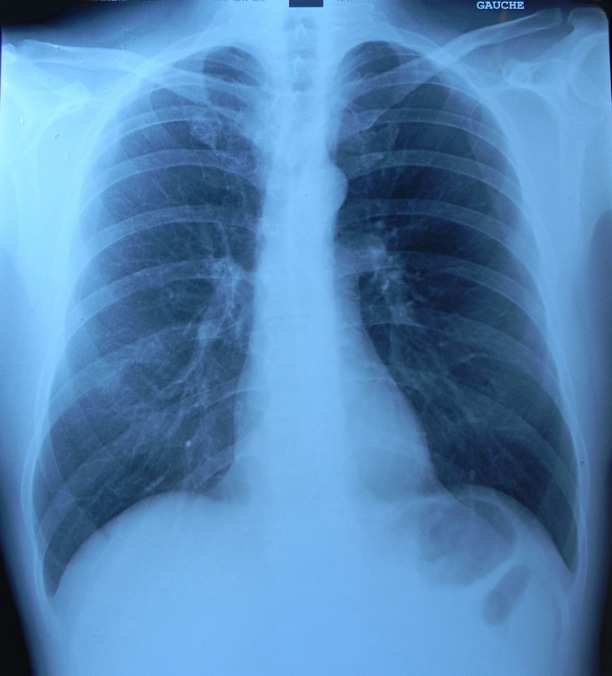

Analyse de radiographies

Radiologie

Analyse différentes radiographies. Essaye de reconnaître:

les différentes parties représentées: os, articulations,...

les malformations, les déplacements, les fractures.

l’âge des sujets: zones de croissances.

La radiographie est une technique qui utilise la différence d’absorption des rayons X par les tissus. Les os sont particulièrement opaques à ce rayonnement et se détachent des tissus environnants. c’est une technique qui a fait ses preuves pour détecter des fractures et des fissures de l’os..